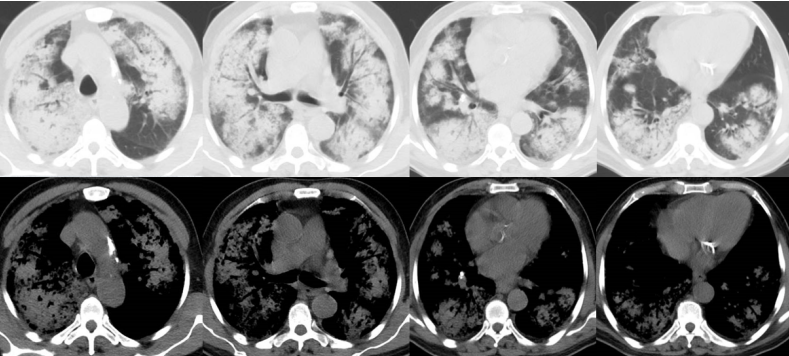

复查胸部CT可见病变较前进一步吸收(图9)

图片

图9 患者胸部CT改善情况